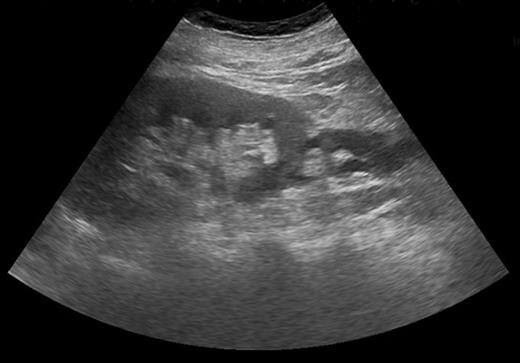

Blood tests revealed a Stage 3 acute kidney injury (baseline renal function was normal) with raised inflammatory markers and elevated PSA compared with baseline (Table 1). A mid-stream urine specimen sent for microscopy, cultures and sensitivities yielded no growth of organisms. A bedside bladder scan revealed a bladder volume of >999 ml, necessitating the insertion of a urethral catheter with a residual volume of 2.4 l, and intravenous antibiotics were commenced. An ultrasound scan (USS) of the urinary tract was performed to evaluate for the presence of hydronephrosis; but while this demonstrated a minor dilatation of the left renal pelvis, it also found a shallow fluid collection around the left kidney extending into the left lateral retroperitoneum, separate from the left psoas muscle (Fig. 1). In the urinary bladder, there was an irregular 4 cm mass on the left posterolateral aspect. In view of the findings, an urgent flexible cystoscopy was performed, revealing a massive median lobe of the prostate protruding up and back into the bladder; the ureteric orifices were not visualized because of this, and the bladder mucosa was normal. The patient subsequently underwent a computed tomography (CT) urogram, which showed bilateral fullness in the pelvicalyceal systems and confirmed a 4.8 × 4.4 × 2.8 cm fluid collection adjacent to the lower pole of the left kidney as detected on the USS, with perinephric stranding. The fluid collection was demonstrated to be extravasated urine on the delayed post-contrast images arising from a defect in the left proximal ureter, and extending down the left paracolic gutter (Figs 2 and 3). The massive prostate was also demonstrable (Fig. 3).

Axial section CT image demonstrating defect in left proximal ureter from which contrast is extravasating, with perinephric fluid collection and fat stranding.

Severe intractable abdominal pain similar to that attributed to renal colic is the most observed presentation of ureteral rupture [1, 6], and its presence is confirmed on imaging, which may be performed to investigate other causes of pain. CT scan of the urinary tract with a delayed excretory phase of contrast is likely to be the most used means and can determine the presence of extravasation, likely location of rupture and extent of urinoma or abscess formation, as well as the nature of the obstructing lesion. If retrograde ureteral stent placement is to be performed, then pyelography can be performed at the same time to confirm CT findings. Ultrasonography has a limited role for detecting ureteral pathologies but was key here in detecting a perinephric fluid collection and possible bladder mass, which led to further investigations.